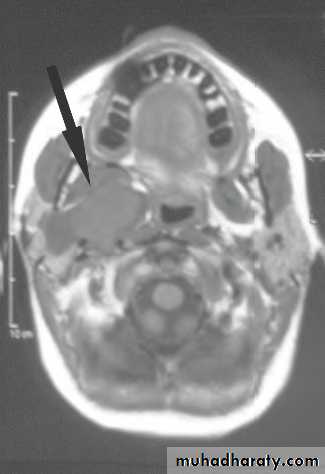

May present with multiple parotid cysts which cause gross parotid swelling and facial disfigurement.

CT&MRI; characteristic Swiss cheese appearance of multiple large cystic lesions.

The swollen glands usually painless and may regress on the institution of antiviral therapy.Cysts may be aspirated